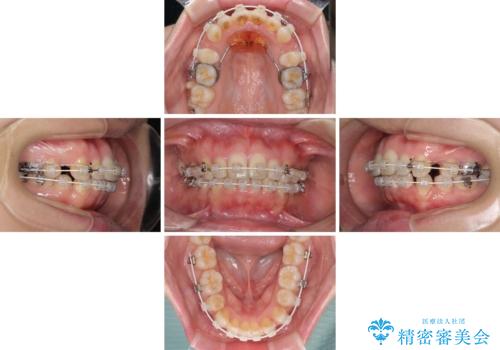

- 審美装置

- 2年4ヶ月

- 10-30回

上下左右第一小臼歯4本を抜歯し、ワイヤー装置にて口元を引っ込めるよう矯正治療を行うこととしました。